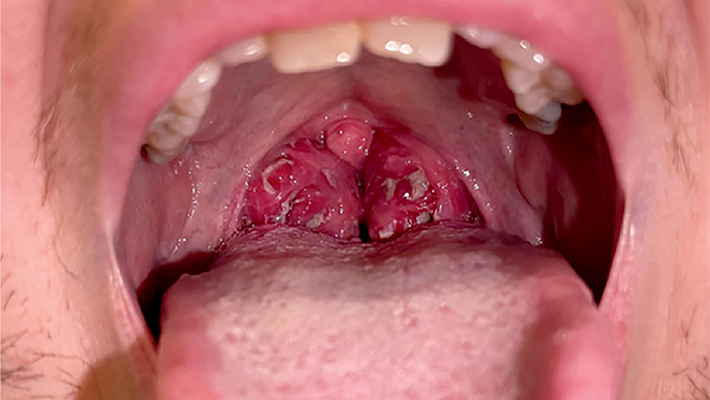

Вирус Эпштейна-Барр взаимодействует с клеткой так, что та начинает активно делиться и вырабатывать новые вирусные частицы. В результате заметно ослабевают различные звенья иммунной системы, в частности, клеточный и гуморальный иммунитет. Одно из неблагоприятных последствий таких изменений — активация патогенных бактерий, из-за чего у больного может развиться, например, гнойный тонзиллит.

- тонзиллит;

Среднетяжелый тип характеризуется более высокой температурой, выраженным тонзиллитом, заметным увеличением лимфоузлов и печени, а также умеренным увеличением селезенки. В крови обнаруживаются атипичные мононуклеары. У пациента ухудшается общее самочувствие и снижается работоспособность.

- гнойный тонзиллит;

Симптомы инфекционного мононуклеоза формируются не сразу, и на раннем этапе их легко принять за обычную простуду. Инкубационный период обычно составляет от одной до четырех недель. Затем разворачивается клиническая картина болезни, которая напоминает затянувшуюся вирусную ангину или тяжелую ОРВИ. Для врача и пациента настораживающим сочетанием являются высокая температура, выраженный тонзиллит, увеличение лимфатических узлов, а также увеличение печени и селезенки.

- боль в горле, затруднение глотания, налеты на миндалинах;

В начале болезни клиническая картина может выглядеть как обычная ангина, поэтому важно вовремя провести клинический анализ крови и обратить внимание на атипичные мононуклеары (измененные лимфоциты вследствие инфекционного процесса). Именно атипичные мононуклеары помогают заподозрить инфекционный мононуклеоз и отличить его от бактериальной инфекции.

При осмотре врач оценивает состояние лимфоузлов, миндалин, печени, селезенки, а также фиксирует наличие сыпи. Уже на этом этапе специалист с большой долей вероятности может предположить мононуклеоз. Однако для подтверждения диагноза нужны лабораторные и инструментальные исследования.